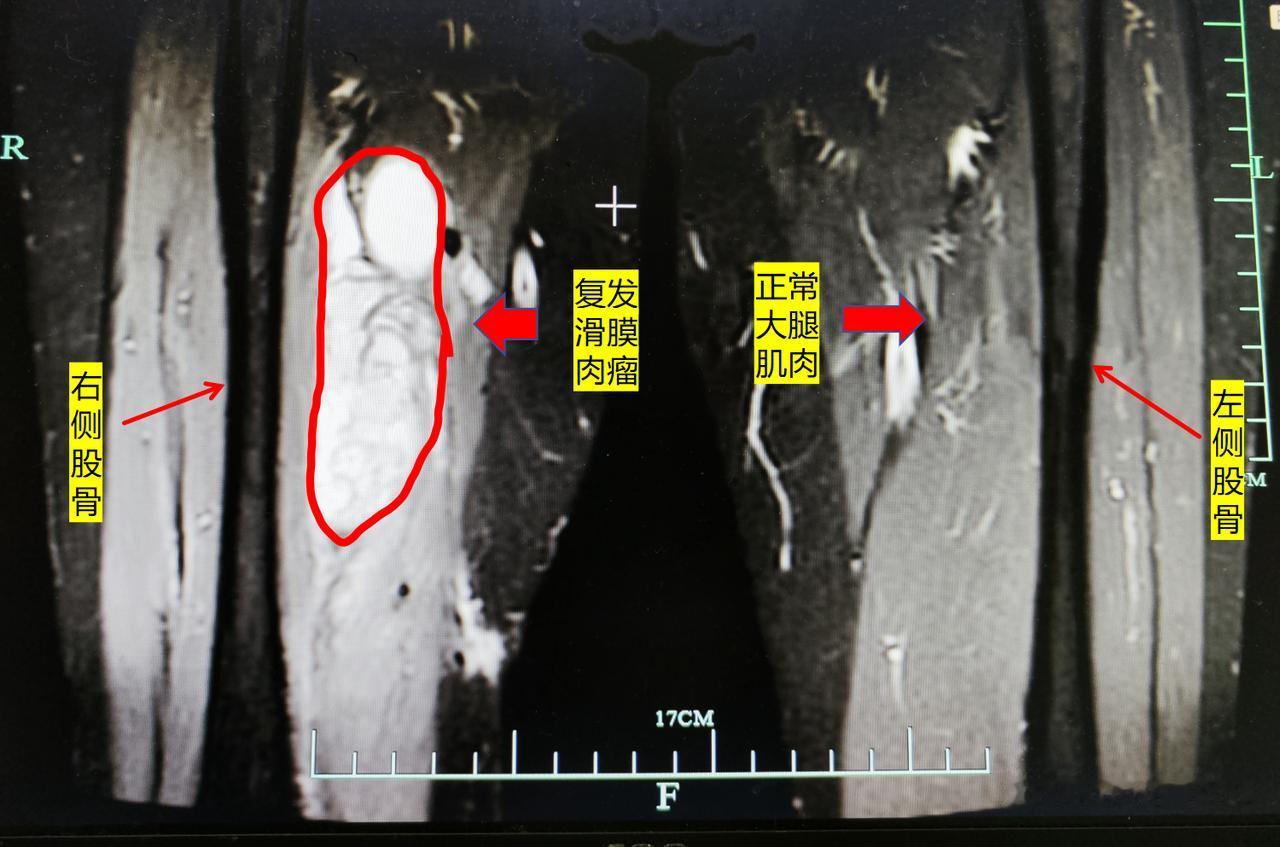

这是我们海扶刀治疗的一名滑膜肉瘤术后复发的患者,病人是一名退休警察。 3年前因滑膜肉瘤在上海长征医院行手术切除,右大腿留下了十多厘米巨大的疤痕,术后行动也有所影响。 这次因滑膜肉瘤术后复发,在了解到海扶刀可以无创消融肉瘤后,至我们中心进行治疗,术前显示病灶血流丰富。 海扶刀治疗后第二天复查,肿瘤坏死明显,病人也没有留下任何伤口,第二天就恢复手术前状态。 患者一直在说要是早知道海扶刀治疗这么轻松,效果这么确切,就应该不选择开刀,首选无创治疗了。恶性纤维肉瘤 海扶刀